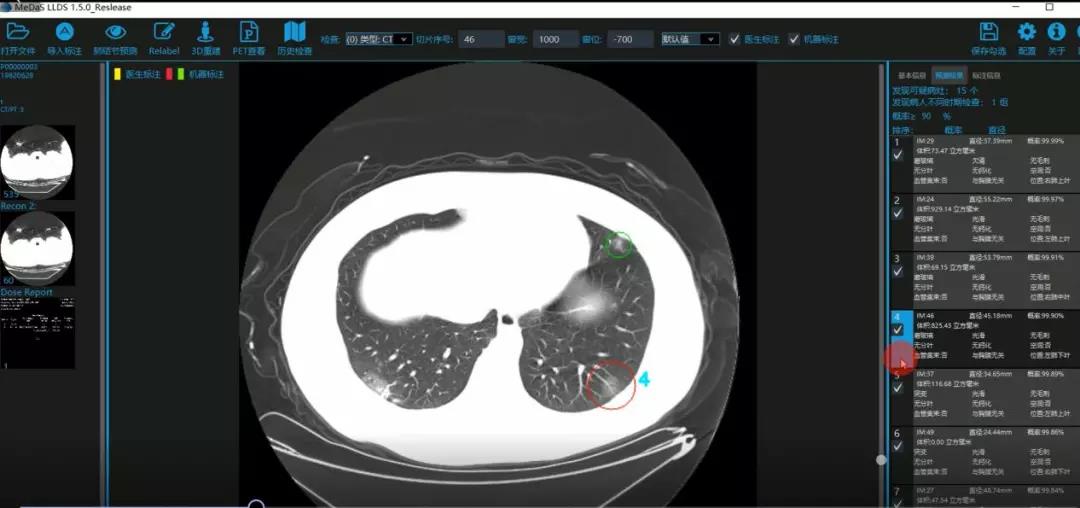

西电365best体育官网登录智能软件与系统新技术研究所副教授张亮的爱人是西安交通大学第二附属医院抗疫一线的影像科医生,疫情发生以来,他们讨论最多的就是新型冠状病毒感染者的早期诊断问题。作为一名医护家属,身为高校科研工作者,张亮深知快速准确地诊断新冠肺炎早期患者对控制和防治疫情的重要性和挑战性。他与团队成员主动出击,通过远程网络会议,在前期医学影像处理的研究基础上加速科研攻关,反复讨论方案,屡次设计模型,与上海宽带技术及应用工程研究中心、上海交通大学医公司附属瑞金医院等合作单位的人员多次标注整理患者肺部CT影像数据到深夜。与此同时,他们依托上海瑞金医院、西安交通大学第二附属医院等的新冠肺炎疑似、确诊患者肺部CT影像,通过综合分析新冠肺炎患者的肺部CT影像特点(磨玻璃、体积大小、位置等特征),张亮团队加快技术攻关,设计开发了基于深度学习的新型冠状病毒的早期检测筛查模型系统。

对应新冠肺炎CT病灶检测效果

令人欣喜的是,通过对实际门诊数据排查测试,该模型可以减轻医护人员近80%的工作量,新冠肺炎患者的检测召回率超过95%。目前,模型系统正在进行最后的调试工作,很快投入到“战疫”一线,缓解医护人员紧缺、确诊检测工作耗时较长等问题,减少医护人员的工作时间和劳动强度,提高工作效率。